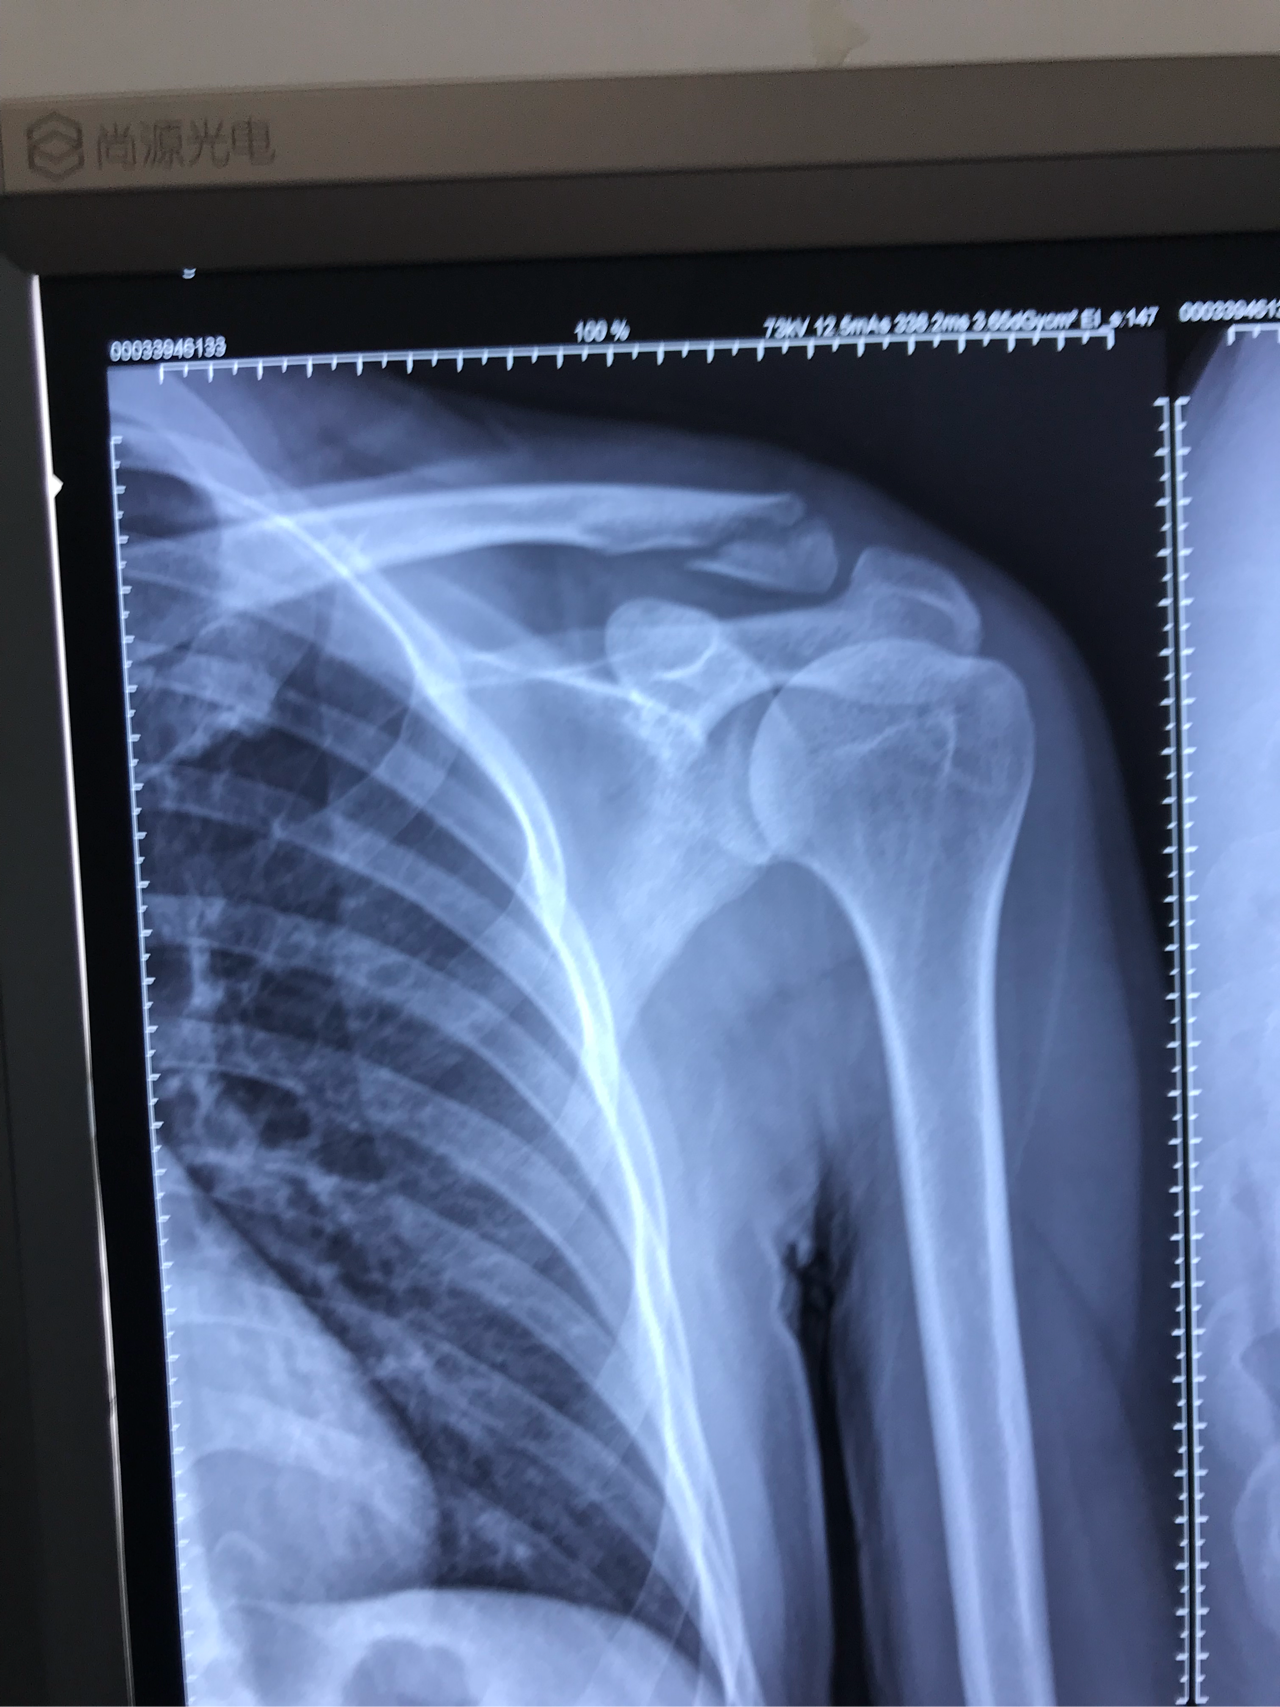

dr片显示:左锁骨远端骨折

图片尺寸2752x2752